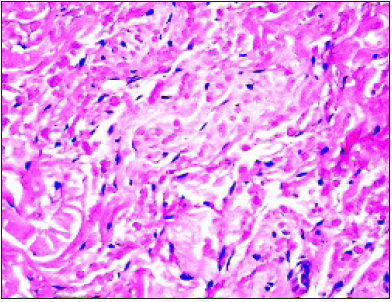

Typically, elastofibroma is localized within subcutaneous tissue and skeletal muscle of the dorsal surface of the shoulder joint, abutting the inferior border of scapula. On account of the characteristic location, the neoplasm is cogitated as elastofibroma dorsi. Elastofibroma dorsi arises from connective tissue of the chest wall and is configured of collagen bundles [2]. Classic site of emergence of elastofibroma is scapular region between sixth and eighth ribs and apex or inferior angle of scapula beneath the serratus anterior, latissimus dorsi and levator scapulae muscles. Majority (90%) of neoplasms are predominantly situated within peri-scapular, subscapular or infra-scapular region beneath rhomboid major and latissimus dorsi muscle, deep-seated to the serratus anterior. Additionally, sites such as the axilla, oral cavity, ischial tuberosity, greater trochanter, posterior elbow, stomach, rectum, omentum, orbit, hand, foot, deltoid muscle, infra-olecranon, thoracic wall, spinal canal, gluteal and inguinal region, thigh, periosteum, mediastinum or cornea are incriminated [2,3]. The neoplasm is commonly discerned within the fifth decade, in adults exceeding > 50 years with an age range of 51 years to 79 years and a mean age of tumour discernment at 68.4 years. Tumefaction discerned in children and infants is extremely exceptional [2,3]. A female predilection is observed. Elastofibroma commonly appears within subscapular region of thoracic fascia in around 24% of adult females and roughly 11% of adult males exceeding 58 years. History of intense physical labour or repetitive activities can be elicited. Elastofibroma probably represents an exaggerated response to trauma or friction (Figure 1). Racial predilection is denominated with enhanced disease incidence in Japanese individuals [2,3]. Although bilateral, the lesion is frequent discerned upon the right side. Bilateral lesions are discerned in roughly 33% of the subjects although neoplasms may be non- synchronous. Besides concomitant infra-scapular and infra- olecranon lesions, multiple lesions of elastofibroma are uncommonly delineated [2,3]. Although considered exceptional, elastofibroma demonstrates a variable disease prevalence of around 2.73%, as discerned with computerized tomography and nearly 24% upon autopsy of the geriatric population. Tumour monitoring for a duration of one month to 30 months with a mean period of 8.6 months demonstrates an absence of residual clinical symptoms or localized tumour reoccurrence [2,3]. As the enlarged, soft tissue pseudo-tumour is deep-seated within deep fascia, often exceeds > 5 centimeters magnitude and is intensely adherent to circumscribing bone or soft tissue, possible occurrence of soft tissue sarcoma requires exclusion [2,3].

Figure 1:Elastofibroma delineating fascicles of elastic tissue, skeletal muscle fibres, collagen tissue and mature adipose tissue cells.